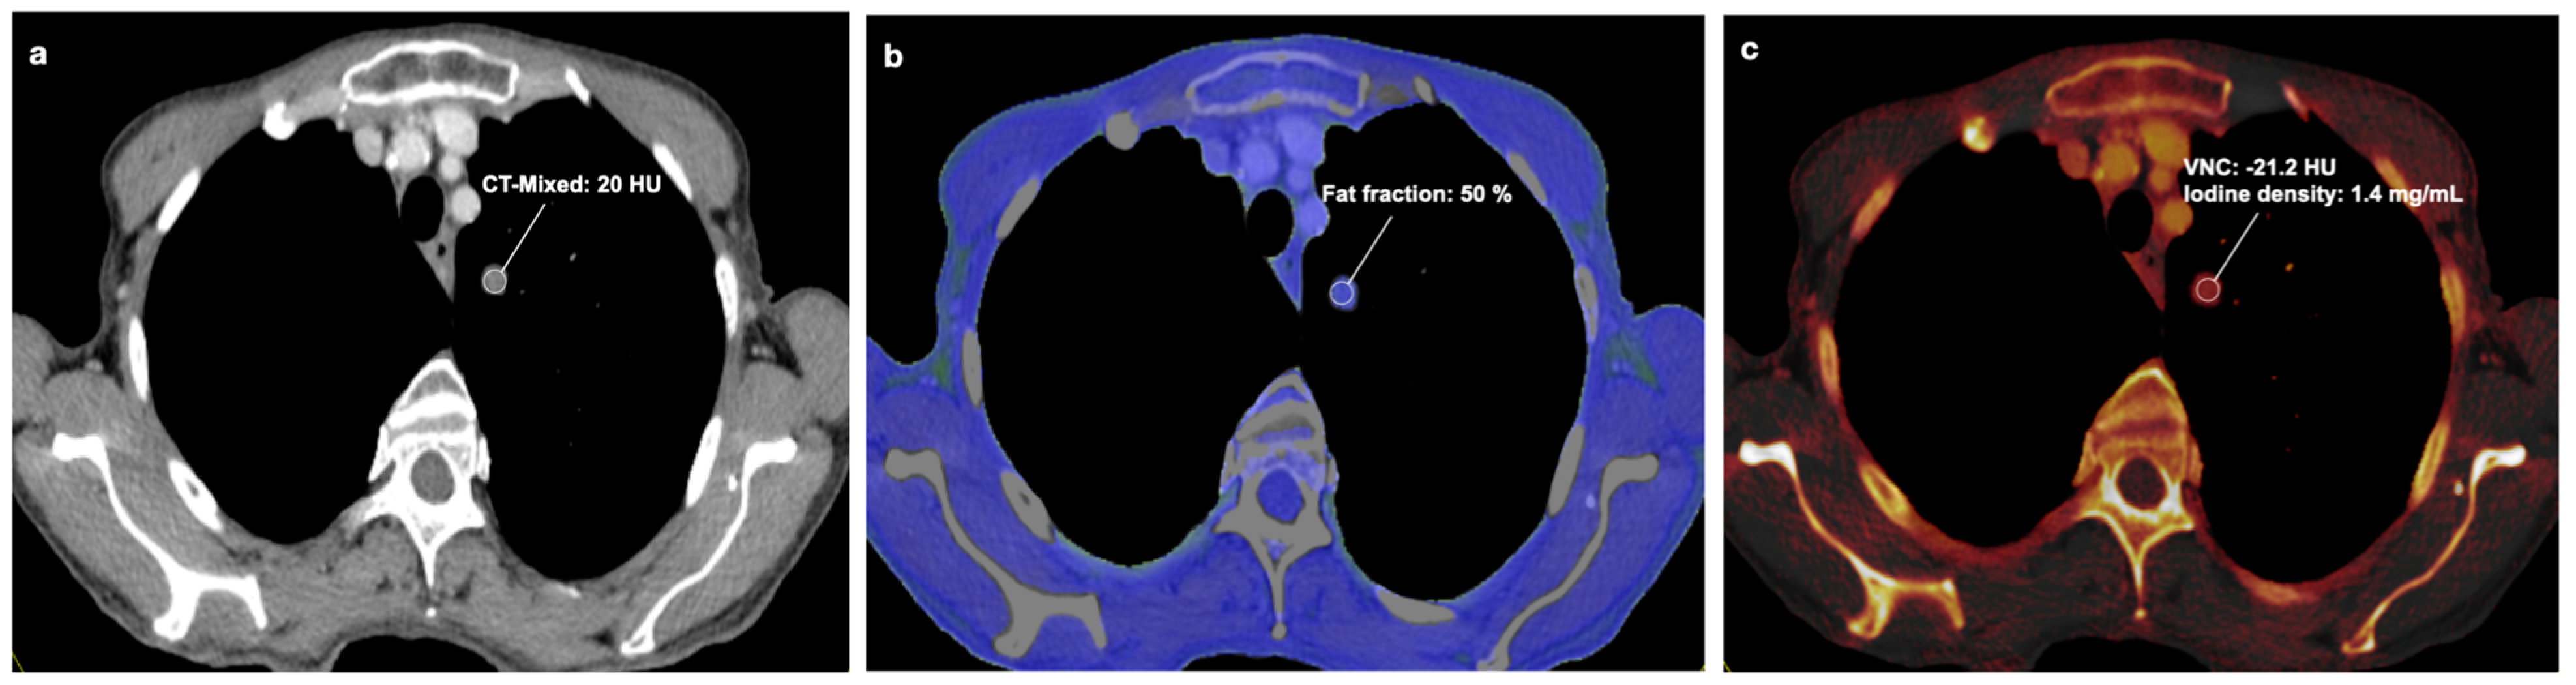

3.2. DECT Image Analysis